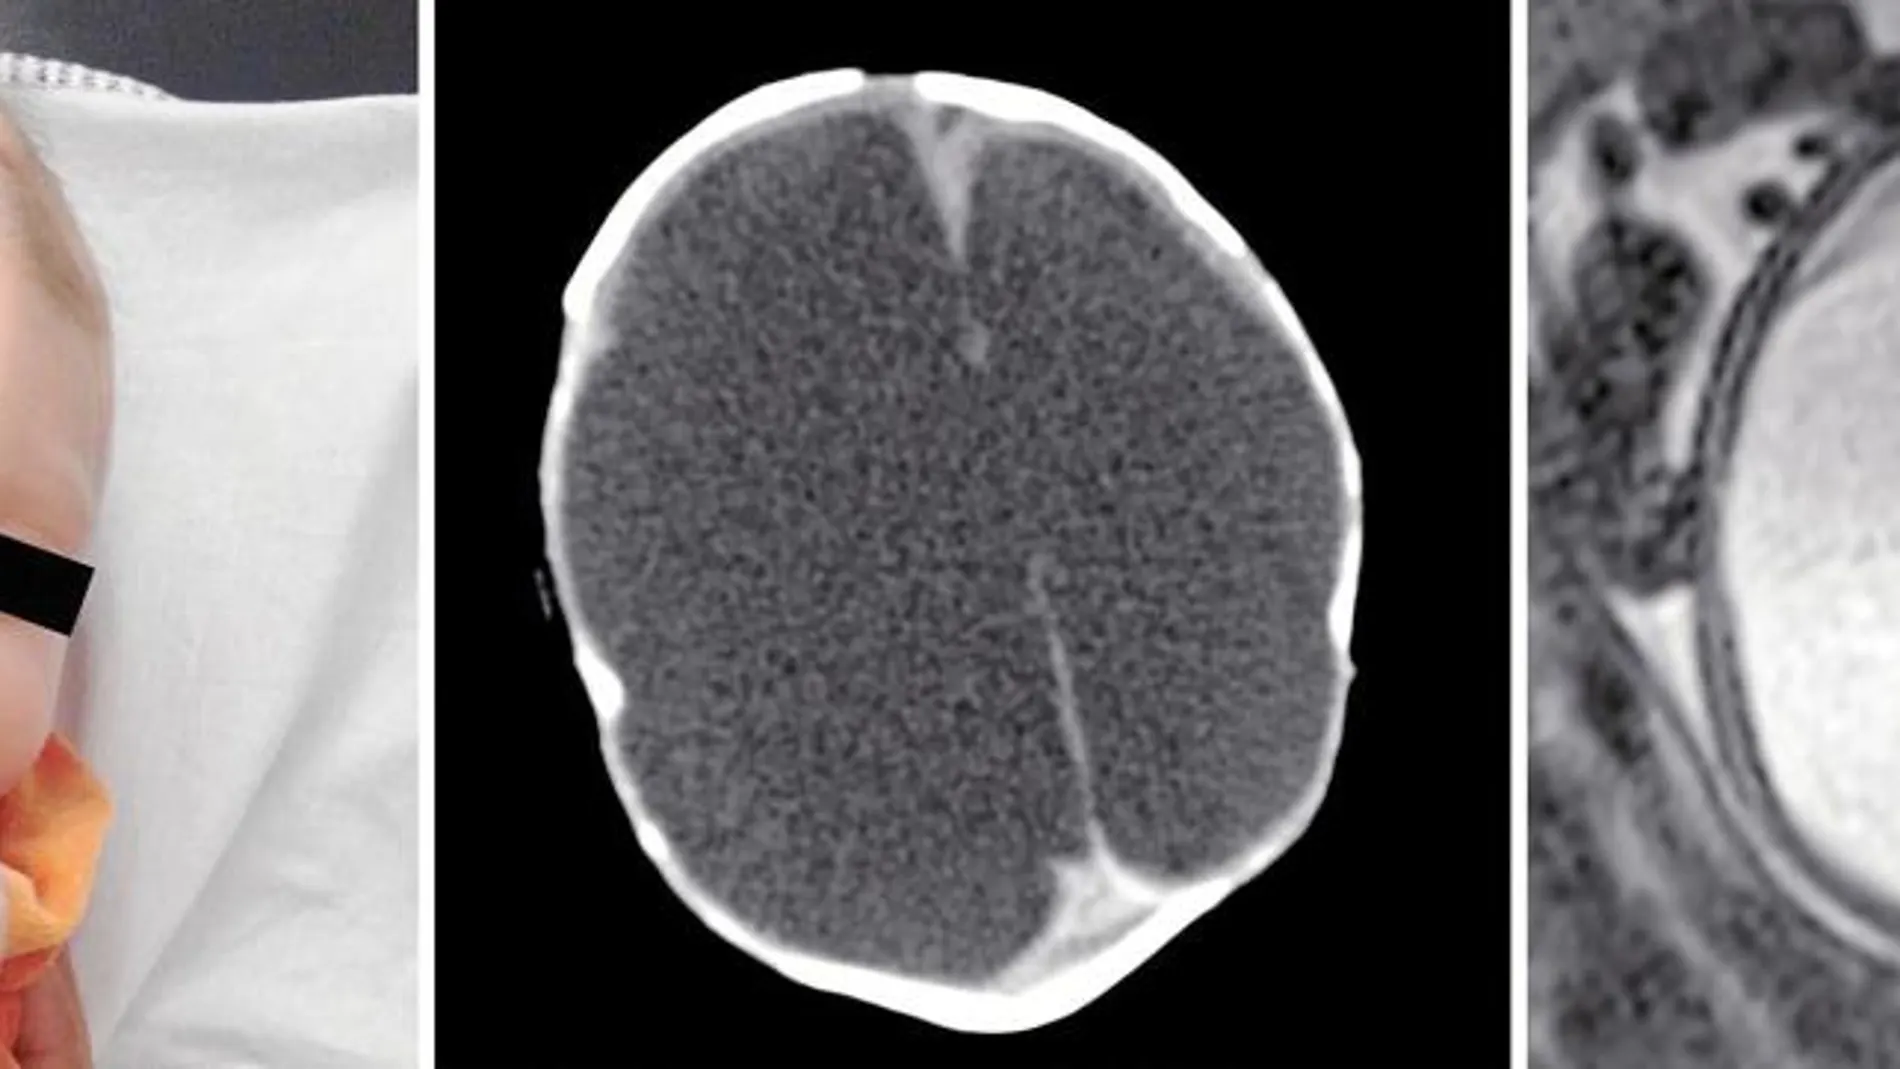

Un amplio estudio de las imágenes de ultrasonido de 45 bebés cuyas madres dieron positivo en el virus demuestra cómo éste ataca a todas las zonas cerebrales del feto. Es capaz de destruir el cuerpo calloso que une los dos hemisferios

Un amplio estudio de las imágenes de ultrasonido de 45 bebés cuyas madres dieron positivo en el virus demuestra cómo éste ataca a todas las zonas cerebrales del feto. Es capaz de destruir el cuerpo calloso que une los dos hemisferios

En cada una de las 75 imágenes que se incluyen en la investigación se refleja cómo el virus destruye, sin piedad, algunas de las partes clave para el futuro desarrollo del feto. Las dos imágenes que ilustran este artículo son las de dos hermanas gemelas, de 14 semanas de gestación. Su madre, de 24 años, sufrió la característica erupción en la novena semana de embarazo. Como exponen los investigadores, los dos bebés padecen calcificaciones, así como una acumulación de piel en la región occipital que «demuestra que el cerebro, en un primer momento, iba a ser más grande de lo que finalmente es», afirman los autores. Sin embargo, uno de los problemas que han detectado al analizar la conformación de sus cerebros es la falta de cuerpo calloso, uno de los tejidos más importantes del cerebro. «Si estas fibras no existen, que son las responsables de unir las dos partes del cerebro, significa que el cerebro del bebé no va a poder cumplir con la mayoría de sus funciones», explica Máximo Vento, presidente de la Sociedad Española de Neonatología. Para el doctor Vento estas imágenes no hacen más que confirmar la gravedad de la enfermedad. «Lo que consigue el virus es desestructurar el cerebro del feto», sostiene.

Gracias a este amplio estudio, los médicos también han sido capaces de detectar otras zonas a las que el virus ataca. Como el cerebelo que, en la mayoría de las imágenes aparece dañado y que juega un papel primordial en el desarrollo del habla, el equilibrio y la movilidad. Y es que en muchas de las fotografías que se han publicado de bebés con microcefalia –esta calificación no es más que la punta del iceberg, ya que sólo se refiere al reducido tamaño del cráneo del bebé, cuando el daño real es el que el flavivirus realiza en su interior– se les ve con poca movilidad, con los bracitos pegados a su cuerpo. Esta actitud también la provoca el zika. «Al afectarle al cerebelo, el cerebro no manda las indicaciones necesarias a los músculos para mantener el tono muscular y pueden atrofiarse», añade Vento. De ahí la importancia de la fisioterapia para estos niños.

Otra de las zonas cerebrales afectadas son los ganglios basales, responsables de las emociones y del desarrollo cognitivo de los fetos. A ello se suma que, casi todos los bebés que se analizaron sufren problemas en el córtex producidos por pequeñas calcificaciones que no permiten a las neuronas llegar al lugar del cerebro que les corresponde. Este hecho preocupa especialmente a los expertos porque el córtex es una de las regiones que se siguen desarrollando después de nacer y, por lo tanto, con el tiempo podrían surgir nuevos problemas. Y es que, como indica el doctor Vento, lo que consigue el virus es «colonizar el cerebro y frenar el desarrollo del mismo».